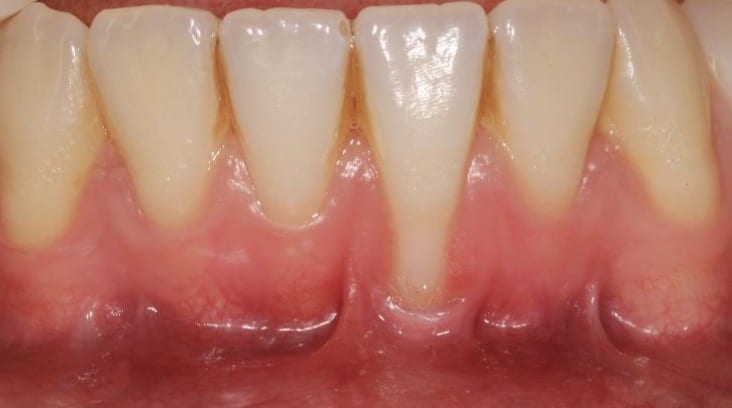

Figure 1. Example of RT1 recession on tooth position 31. Note the reduced keratinised tissue width and prominent frenum attachments.